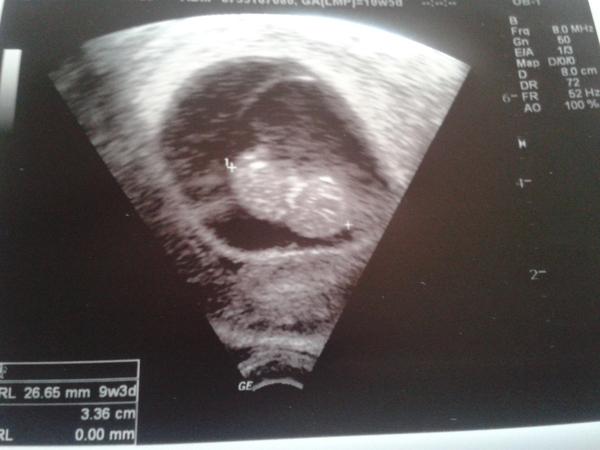

Baby.takze sa hlasime.vcera na sone bolo vsetko supis.mame 26,65 mm a zodpovedame 9+4 aj ked podla ms 10+6 😀 doky Jonas dal iny termin.co uz s nim 😀 a mame fotecku.len sa mi nejak neda pridat cez mobul ani do albumu :-/